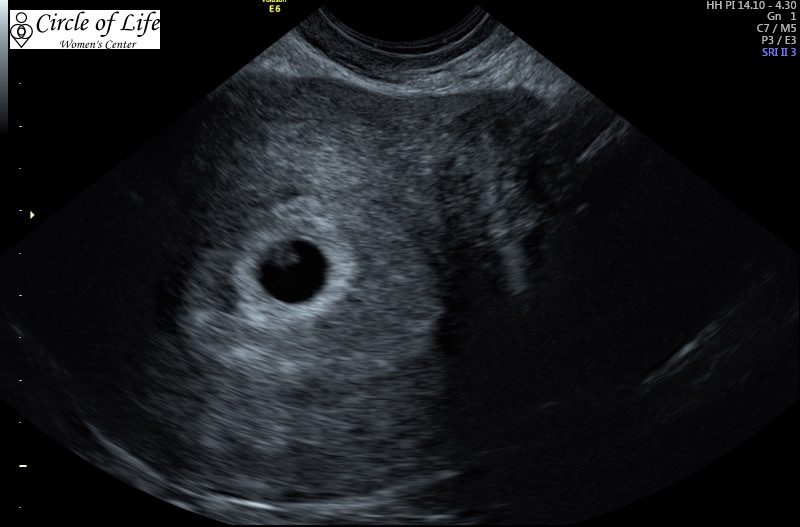

I posted this in the weekly appointment thread, but I'll put it here too! Look at that little sea horse! Was thrilled! Measured 6 weeks 6 days (to the DAY of ovulation!) and had a HR of 128. DDs was higher when I had my first with her (she was also two days older), so I wonder if that means anything. Doctor said the heart rate was good though, so it must not be too low